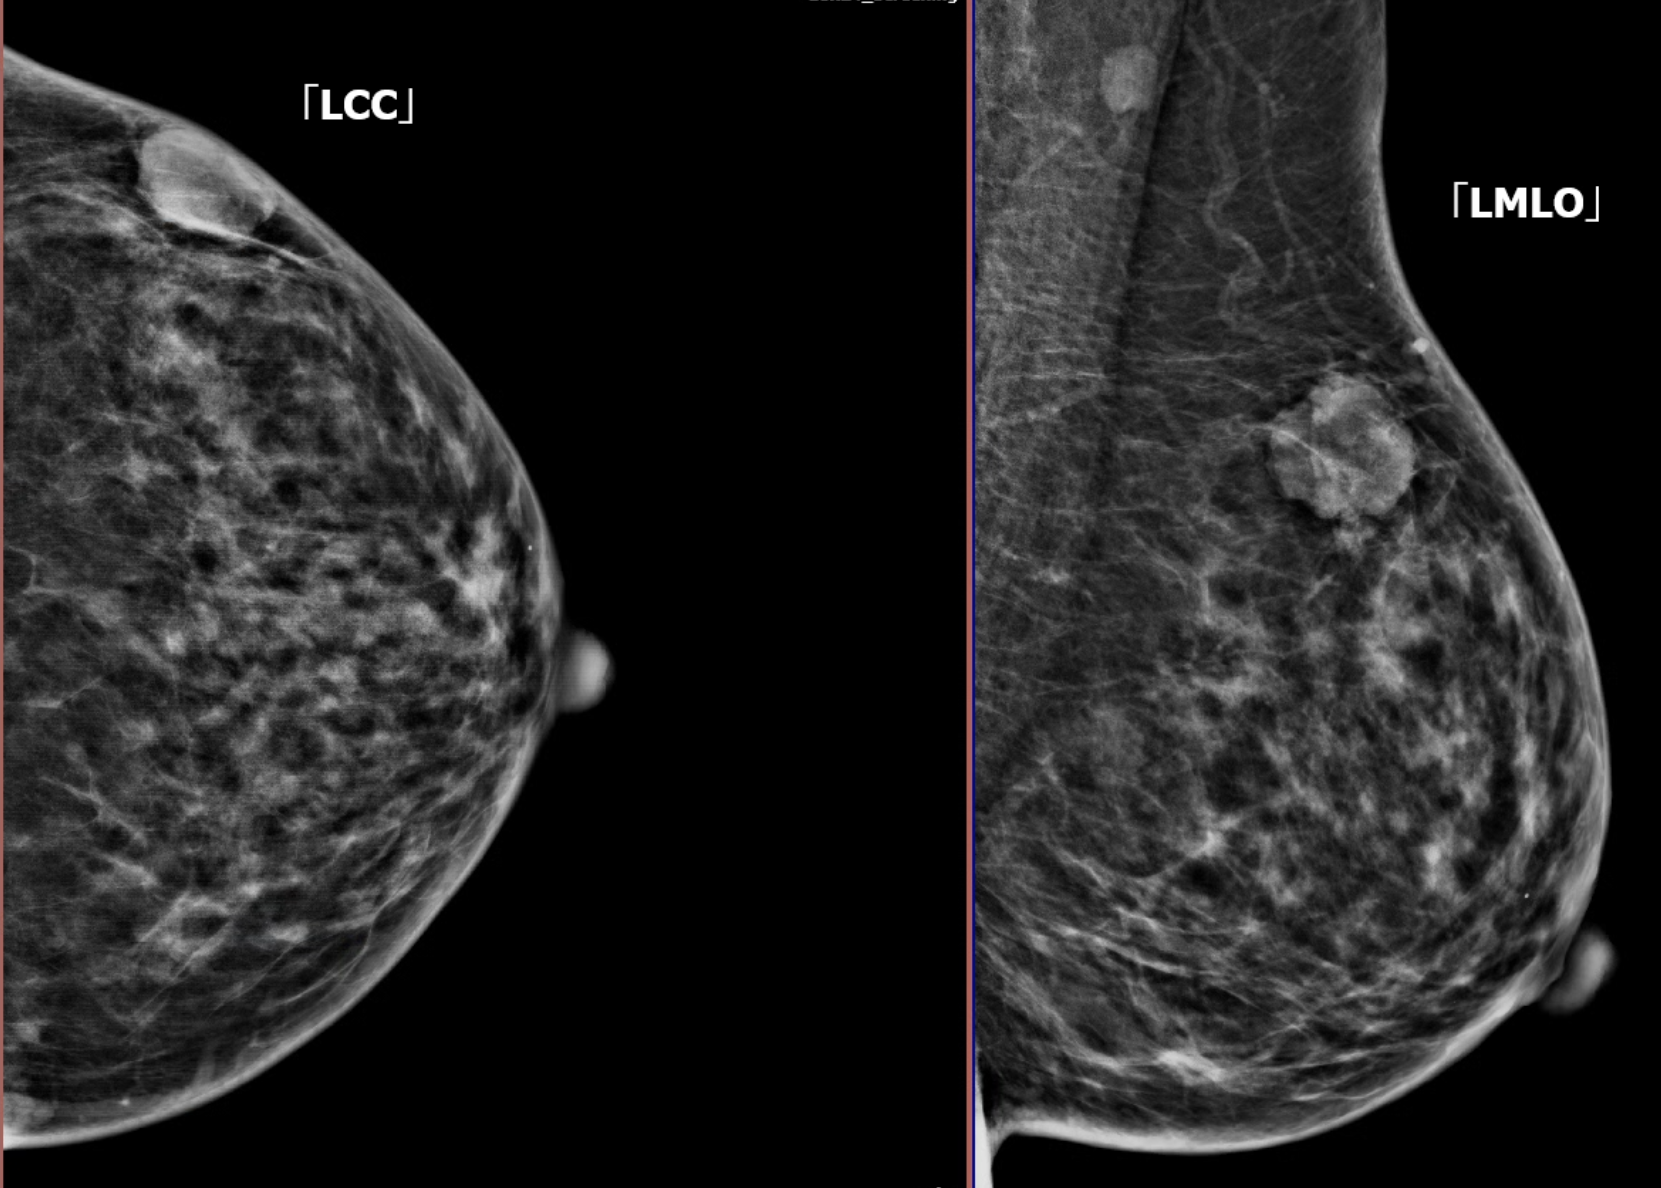

Kết quả nhũ ảnh

So sánh BIRADS

- Khối bầu dục, giới hạn rõ

- Không xáo trộn cấu trúc

- Không vi vôi hóa

👉 Phân loại: BIRADS 3 (có khả năng lành tính)

➡️ Sự khác biệt này cho thấy tính không đồng nhất giữa các phương pháp chẩn đoán.